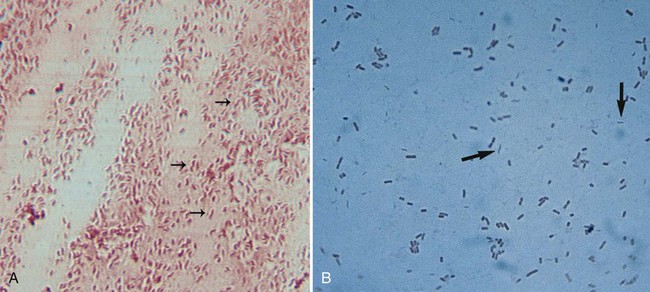

Кампилобактер фетус: патогенез и инфекции